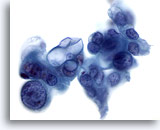

画像 1: 肝FNA – 良性肝細胞 良性肝細胞の小さな集塊。細胞は多角形のものもあれば円形のものもみられ、細胞境界は明瞭です。 核は中心性に位置し、周辺の細胞質は顆粒状を呈しています。細胞質内に色素沈着がみられます。小型の核小体がみられるものの、異型性および高N/C比は認められません。

肝FNA – 良性肝細胞

良性肝細胞の小さな集塊。細胞は多角形のものもあれば円形のものもみられ、細胞境界は明瞭です。 核は中心性に位置し、周辺の細胞質は顆粒状を呈しています。細胞質内に色素沈着がみられます。小型の核小体がみられるものの、異型性および高N/C比は認められません。